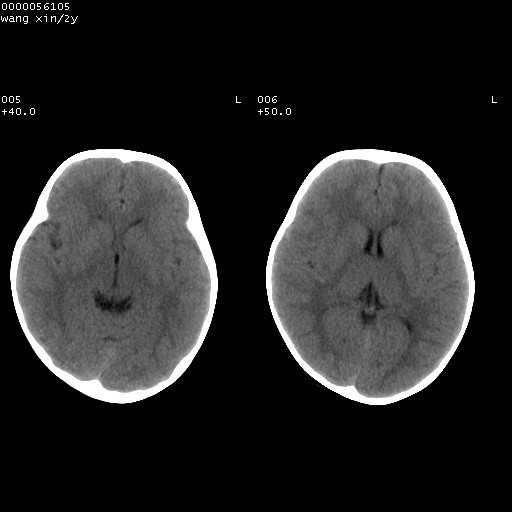

标题: PED1611:F,2Y。右侧额部小包块,光整,质硬,边界清楚,无 [打印本页]

标题: PED1611:F,2Y。右侧额部小包块,光整,质硬,边界清楚,无

病灶临近颅缝,支持考虑表皮样囊肿可能,病灶区要薄扫就好了

右额骨内板压迫性变薄,呈椭圆形膨胀性骨吸收和低密度区,其间可见小斑片状致密影,-支持表皮样囊肿